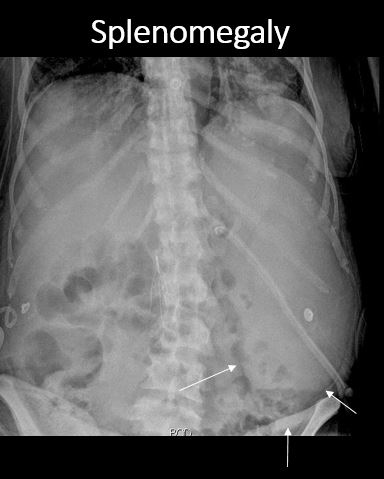

There is splenomegaly. |

No | NA |